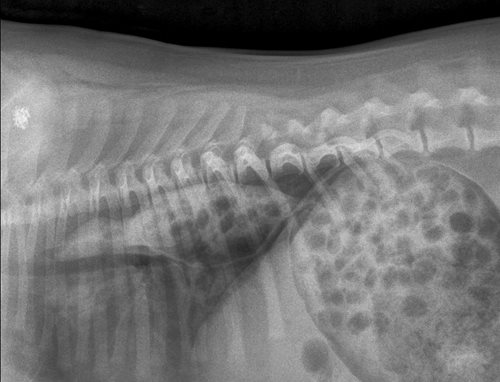

Röntgenfoto's worden ook wel eens gebruikt om te weten hoeveel pups je kan verwachten. We tellen dan het aantal schedel en/of het aantal ruggengraten op de foto. Kan jij zeggen hoeveel pups deze teef verwacht?

Het zijn er drie ;-)